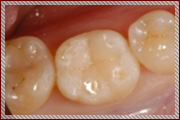

C1~C2の治療:歯の表面と内側を削って詰める治療を行います

単に虫歯を削って詰めるといっても暗くて小さいお口の中で、

患者様の健康な歯を傷つけずに虫歯の部分のみを取り除くことは、

非常に困難な作業です。

そのため従来の肉眼による治療では、

虫歯以外の健康な歯もたくさん削られて治療されていました。

その結果、治療後も歯がしみる、痛いなどの不快症状が残ることがあります。

当院では顕微鏡などの拡大鏡を使用することにより、

健康な歯を削らずに残し、

虫歯になってしまった部分だけを取り除いて

そこに接着材料をつかってきれいに封鎖する

MI治療(Minimum Intervention~最小の侵襲)を行っております。

治療後の不快症状を最小限におさえ、なによりも従来の治療よりも歯を削らないため患者様の大切な歯を長持ちさせることができます。